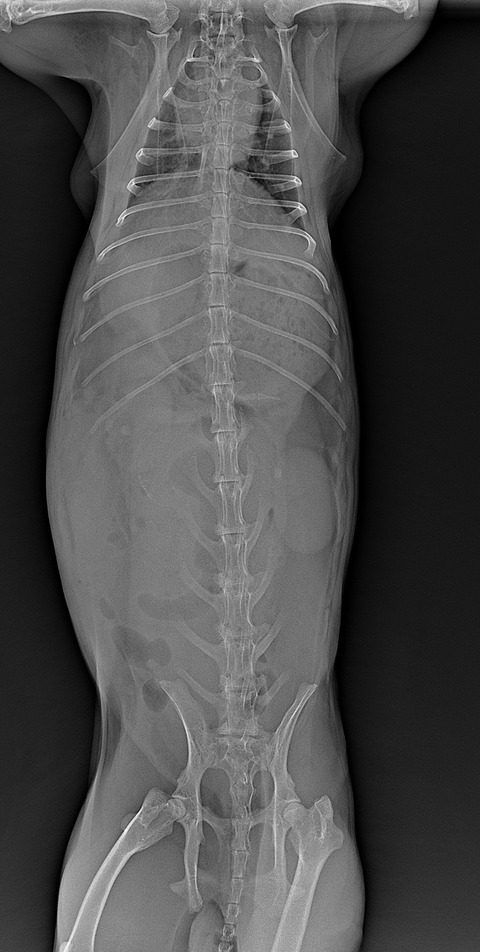

⇩正常なレントゲン像

(⇩正常なサイズの胃)